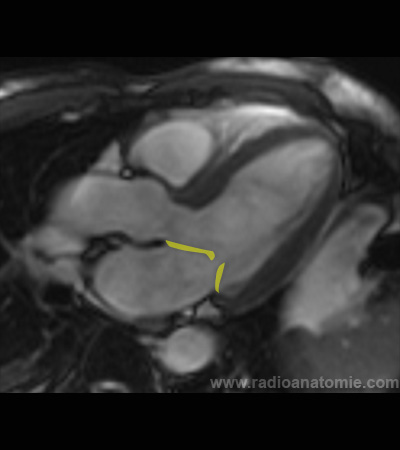

Valve mitrale